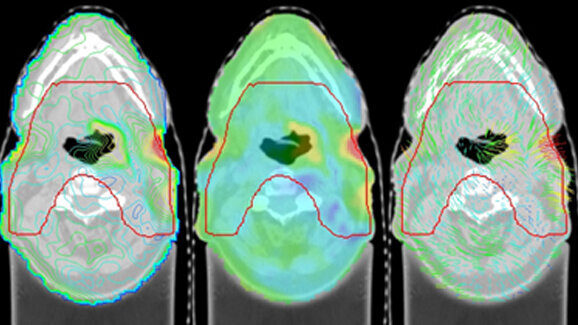

Die in Kooperation mit der Medizinischen Universität Graz entwickelte Software ReDeform© ermöglicht die automatische Auswertung der anatomischen Veränderungen im HNO-Bereich. Beim Vergleich zweier Datensätze von unterschiedlichen Zeitpunkten ist die genaue anatomische Änderung feststellbar, ohne rund 200 Schnittbilder per Hand bearbeiten zu müssen. Mit Hilfe von ReDeform© werden die von der ersten Untersuchung eingezeichneten Konturen für die Bestrahlungsplanung auf den neuen Datensatz transferiert, wodurch eine auf den aktuellen körperlichen Zustand des Patienten angepasste Bestrahlung ermöglicht wird. Unter der Leitung von Klinikvorständin Univ.-Prof. Dr. Karin Kapp und des Medizinphysikers Dipl.-Ing. Dr. Peter Winkler wurde an der Univ.-Klinik für Strahlentherapie-Radioonkologie der Medizinischen Universität Graz eine klinische Studie durchgeführt, die mittlerweile abgeschlossen ist. „Das Resultat dieses gemeinsamen Projekts ist höchst erfreulich. Die vom Forschungsteam der JOANNEUM RESEARCH entwickelte Software ReDeform© ermöglicht einen adaptiven Therapieansatz zur kontinuierlichen Optimierung der Bestrahlungsplanung über die gesamte Behandlungsdauer. Bei der adaptiven Strahlentherapie wird das Bestrahlungsgerät mit 3-D-Röntgenbildgebung gekoppelt. Strahlen werden präziser auf den Tumor gelenkt. Das umgebende, gesunde Gewebe wird dabei vor Strahlenschäden geschont. Die bestrahlte Körperregion ist im Laufe eines Behandlungszyklus ständig unter Beobachtung. Bei Veränderungen der Tumorregion kann sofort nachjustiert werden“, erklärt Dr. Winkler.